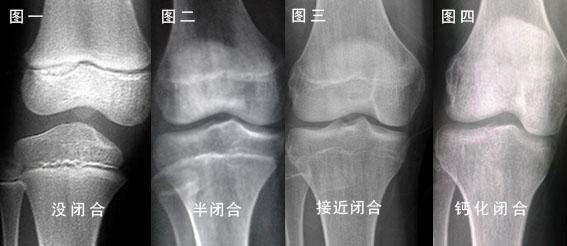

闭合前的骺板是一条透亮的区带,而闭合后透亮区消失,与旁边的骨骺融为一体,如果看到透亮,那恭喜你,还有长高的可能;

如果觉得上面丁香医生的灵魂手绘看不清楚,可以看下面的这个:

图片来自网络,侵删: